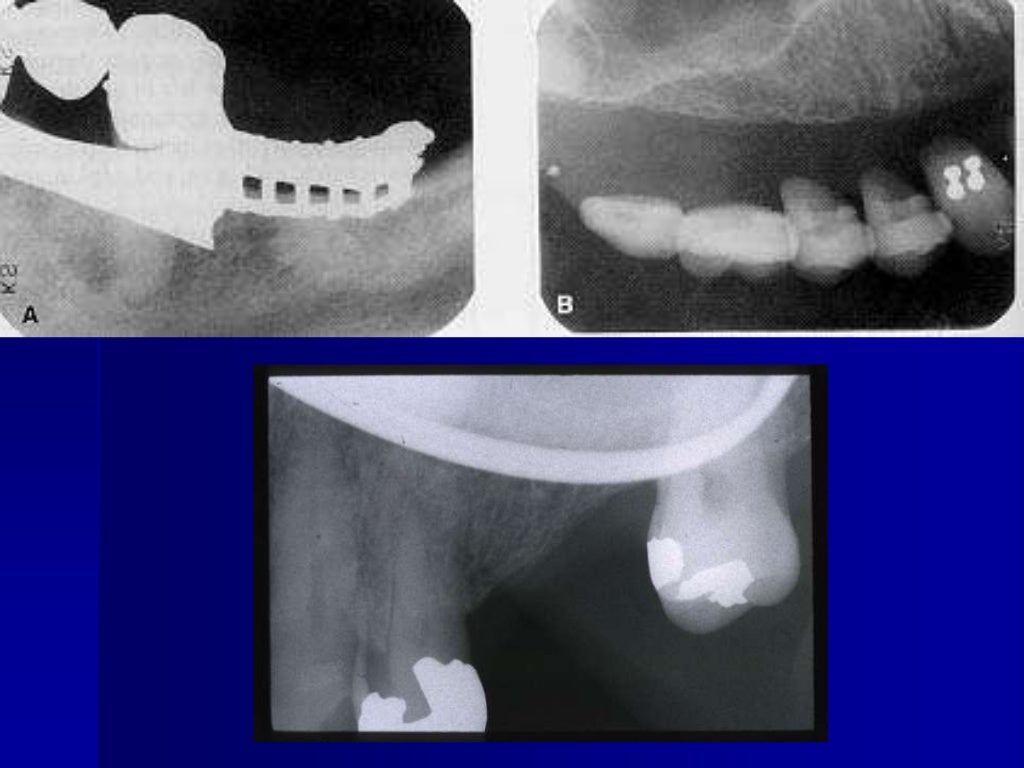

Common Dental Radiographic Errors . Very complex anatomy of maxillofacial region;. radiographs aid in the diagnosis and characterization of the type and extent of disease, but. radiographic errors may be due to technical errors [ errors related to the technique of taking the radiograph] or. radiographic images are especially useful in the diagnosis and treatment of dental caries, periodontal bone loss, periapical pathosis. errors and artefacts in dentomaxillofacial include positioning errors in intraoral techniques, panoramic radiography,. reasons of appearance of technical errors and artefacts in dentomaxillofacial radiology: a common receptor placement error is inadequate coverage of the area to be examined radiographically. in dental radiology, quality control has been wrongly focused on only the control/development of equipment, such as.